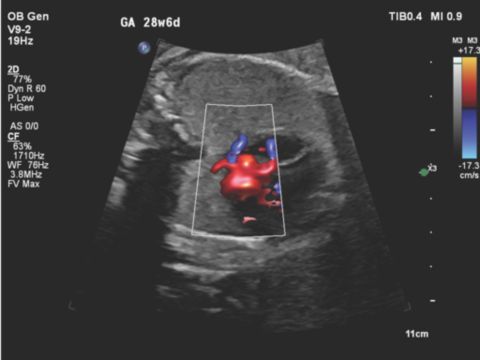

Traditional color flow imaging was suboptimal, however supported no evidence of renal arteries (Figure 4). Using Flow Viewer, the fetal aorta was more easily identified and clearly demonstrated bilateral absence of the renal arteries (Figure 5). The patient was informed of the findings of bilateral renal agenesis, which included a discussion regarding the lack of specific treatment outside of research protocols and the poor prognosis.

V9-2 transducer coronal image of the fetal aorta and absence of bilateral renal arteries using color Doppler with Flow Viewer

Figure 5 V9-2 transducer coronal image of the fetal aorta and absence of bilateral renal arteries using color Doppler with Flow Viewer

In this patient’s case, the fetal diagnosis was not fully conclusive with the use of 2D imaging and traditional color flow imaging on the C5-1 transducer. Our diagnosis of bilateral renal agenesis, which progressed from an initial finding of bilateral multicystic dysplastic kidneys, was aided using Flow Viewer. This color Doppler imaging modality allowed for superior imaging of the fetal aorta and the ability to definitively demonstrate complete and bilateral absence of the fetal renal arteries. In this case, the fetal diagnosis was made with greater accuracy using Flow Viewer advanced color Doppler ultrasound technology, which provided the clinician and the patient a greater degree of confidence in the true diagnosis of bilateral renal agenesis in the fetus.

The latest Philips update to color flow Doppler is the innovative imaging modality Flow Viewer. Flow Viewer is a significant improvement over traditional color Doppler ultrasonography alone (Figures 6, 7 8). In both routine obstetric and complex perinatal care, the availability of Flow Viewer for color flow Doppler ultrasound has remarkable potential to change the healthcare of the pregnant patient and for prenatal diagnosis and management of the fetus. Flow Viewer continues to demonstrate the impressive capabilities of ultrasound through high-quality flow imaging, clearly defined fetal vasculature and cardiac anatomy as well as an enhanced 3D-like realistic image.